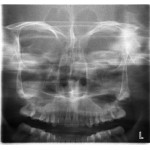

• Programa panorámico estándar: Para producir radiografías precisas y sin distorsiones, la forma de la capa focal ha sido diseñada para seguir científicamente la forma del maxilar y de la mandíbula.• Programa panorámico pediátrico: El programa pediátrico reduce automáticamente el área expuesta,reduciendo en un 20 % la dosis,sin perder información.• Programa ATM doble lateral

• Programa ATM doble PA

• Programa Senos PA

Programa ATM doble lateral PA

El programa doble ATM produce vistas laterales y posteroanteriores de las articulaciones temporomandibulares cerradas y abiertas en una sola radiografía. La imagen radiográfi ca, obtenida por este proceso, permite un fácil diagnóstico de las condiciones de las ATM de un vistazo.